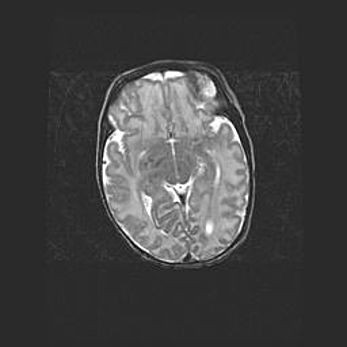

Мальформация Денди-Уокера. Киста задней черепной ямки.

Агенезия мозолистого тела.

Возраст: 2,5 месяца

Вес: 2420 г

Пол: женский

Окружность головы: 37 см

Срок гестации: 32 недели

Мальформация Денди—Уокера — редкий вид патологии ЦНС, представляющий собой врожденный порок развития каудального отдела ствола и червя мозжечка, ведущий к неполному раскрытию срединной (Мажанди) и латеральных (Лушка) апертур IV желудочка мозга. Для этогно синдрома характерна триада симптомов: гипотрофия червя мозжечка и/или полушарий мозжечка, кисты задней черепной ямки, гидроцефалия различной степени. В 70% случаев порок сочетается и с другими аномалиями головного мозга, в частности с агенезией мозолистого тела.